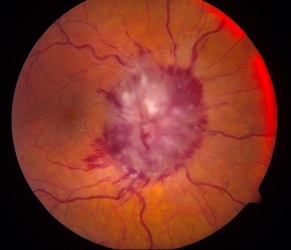

Visual loss at presentation is uncommon, and is usually due to compression or direct invasion of the optic nerves or chiasm, or orbital metastases. This may lead to florid papilledema (Figure 2). Other causes of vision loss include carcinomatous meningitis, infectious meningitis, intrusion into vitreous causing choroidal ectasia, and metastases to the iris. There have been two reports of visual loss in the setting of increased intracranial pressure in the absence of all above features, one in a child[36] and one in an adult.[37]

Figure 2. Frissen Grade V Papilledema from neuroblastoma orbital metastases